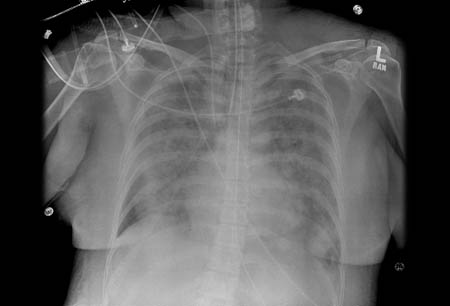

Síndrome do desconforto respiratório agudo (SDRA)

Imagem de radiografia torácica de infiltrados bilaterais em um paciente com síndrome do desconforto respiratório agudo (SDRA)

Do acervo pessoal da Dra. Lorraine Ware; usado com permissão